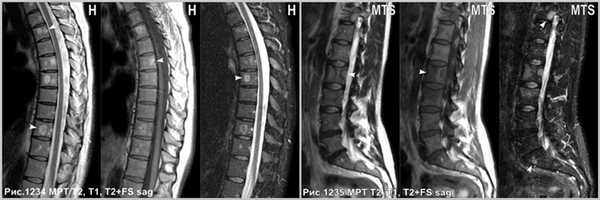

Множественные гемангиомы, поражающие ряд позвонков (головки стрелок на рис.1234). Метастазы, поражающие тела позвонков (головки стрелок на рис.1235).

![heangioma_8]()

На КТ дифференциальный диагноз между метастазом и гемангиомой не представляет сложности в связи с тем, что литический метастаз выглядит в виде округлого участка без чётких контуров, вызывая рассасывание губчатой и компактной костной ткани (головки стрелок на рис.1237), а склеротический метастаз в виде очагов уплотнения костной ткани посреди губчатого вещества тела позвонка (головки стрелки на рис.1238). Гемангиома имеет уплотнённые вертикальные костные балки на фоне разряженной структуры губчатого вещества тела позвонка (звёздочка на рис.1236).